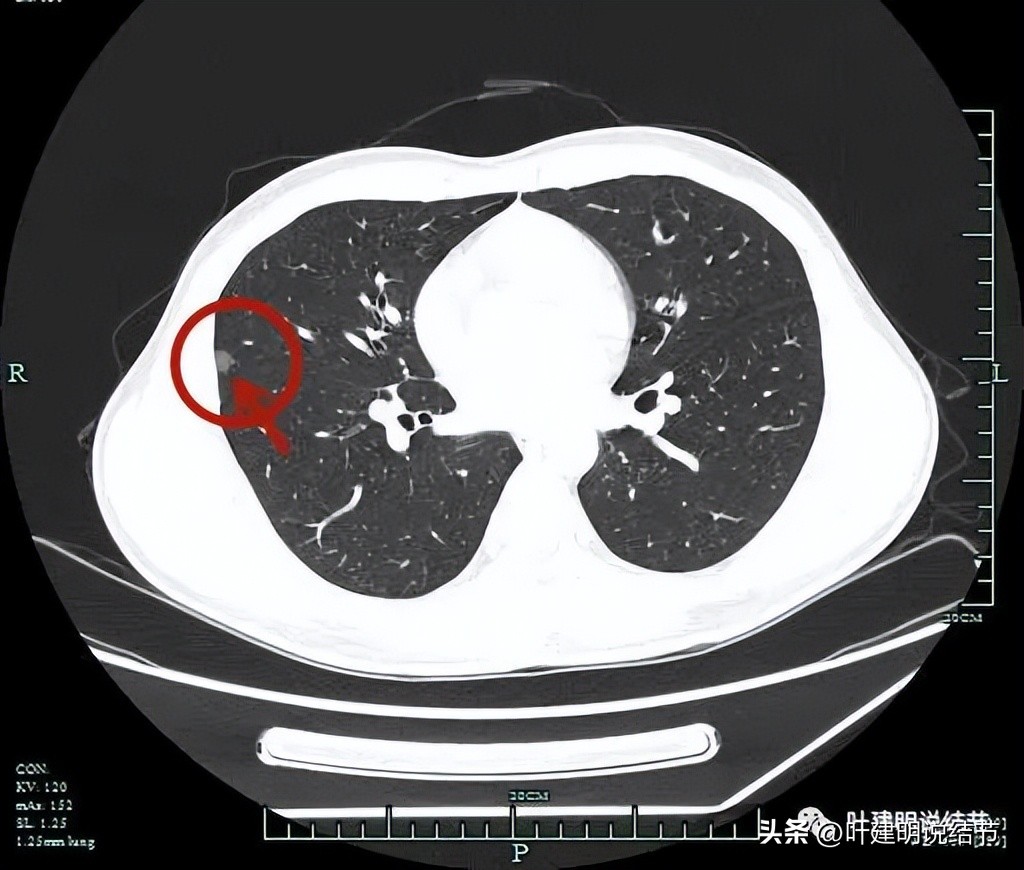

薄层平扫见三处病灶:

病灶1:右中叶磨玻璃结节,瘤肺边界与轮廓非常清楚,一看就是肿瘤范畴的结节,只是实性成分不明显,危险性可能还不算大。